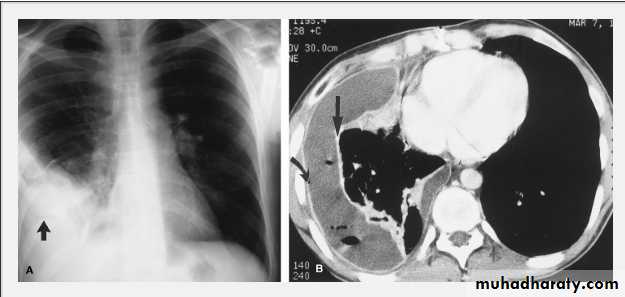

On a posteroanterior chest x-ray (A), the left hemithorax is very dark or lucent because the left lung has collapsed completely (white arrows).The tension pneumothorax can be identified because the mediastinal contents, including the heart, are shifted toward the right, and the left hemidiaphragm is flattened and depressed. A computed tomography scan done on a different patient with a tension pneumothorax (B) shows a completely collapsed right lung (arrows) and shift of the mediastinal contents to the left.